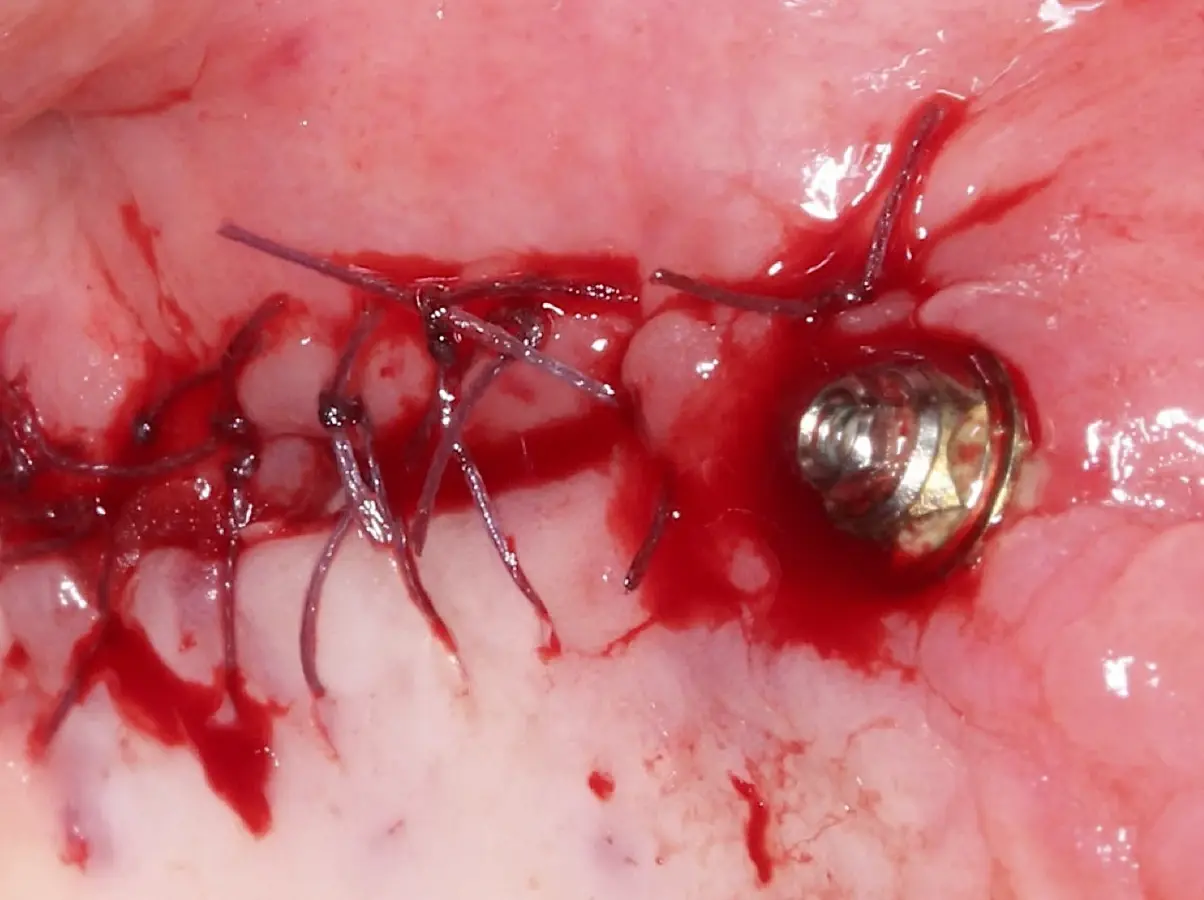

Finalizado el lado izquierdo, continuamos con el levantamiento de piso de seno maxilar del lado derecho.

Figura 22. Afrontamiento de colgajo y sutura.

Figura 23. Delimitación y osteotomía por desgaste de la ventana lateral con el inserto redondo de punta diamantada.

Figura 24. Fractura del bloque óseo con la ayuda de un martillo e instrumento romo.

Figura 25. Introducción del bloque óseo de la pared lateral dentro del seno maxilar: inicio del desprendimiento de la membrana con el inserto de presión hidráulica.

Figura 26. Decolado de la membrana de Schneider hasta la pared medial del seno maxilar (a). Desplazamiento de la pared ósea lateral al interior del seno maxilar transformándose en parte del techo de la ventana o nuevo piso del seno (b).